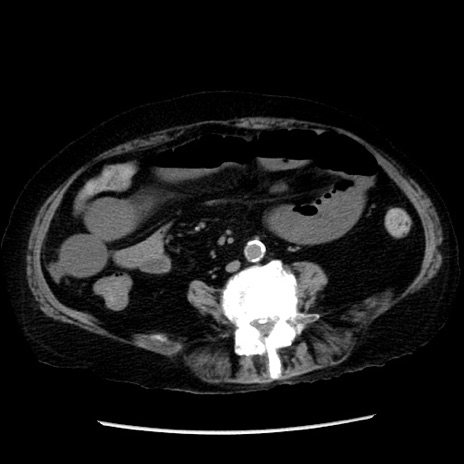

症例14(横断像)

【症例】 90歳代女性

【主訴】 腹痛・嘔吐

【現病歴】今朝から左側腹部痛を認めた。 経過観察していたが、嘔吐を認めたため来院。

【既往歴】 子宮癌術後

【身体所見】 意識清明、BP 127/54mmHg、P 98bpm Sp02 95%(RA)、BT 35.8°C、腹部平坦・軟腸ぜん動音聴取良好、右下腹部圧痛(+) 反跳痛なし

【データ】WBC 9800、CRP 0.46